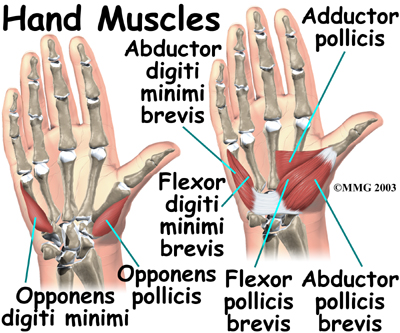

Most of the small muscles that work the thumb and pinky finger start on the carpal bones. connect in ways that allow the hand to grip and hold. Two muscles allow the thumb to move across the palm of the hand, an important function called .

The smallest muscles that originate in the wrist and hand are called the intrinsic muscles. The intrinsic muscles guide the fine motions of the fingers by getting the fingers positioned and holding them steady during hand activities.